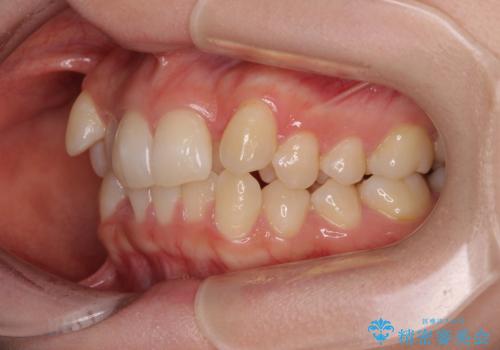

補助装置を併用したおかげで、出っ歯になることなくスムーズに治療を終えることができました。